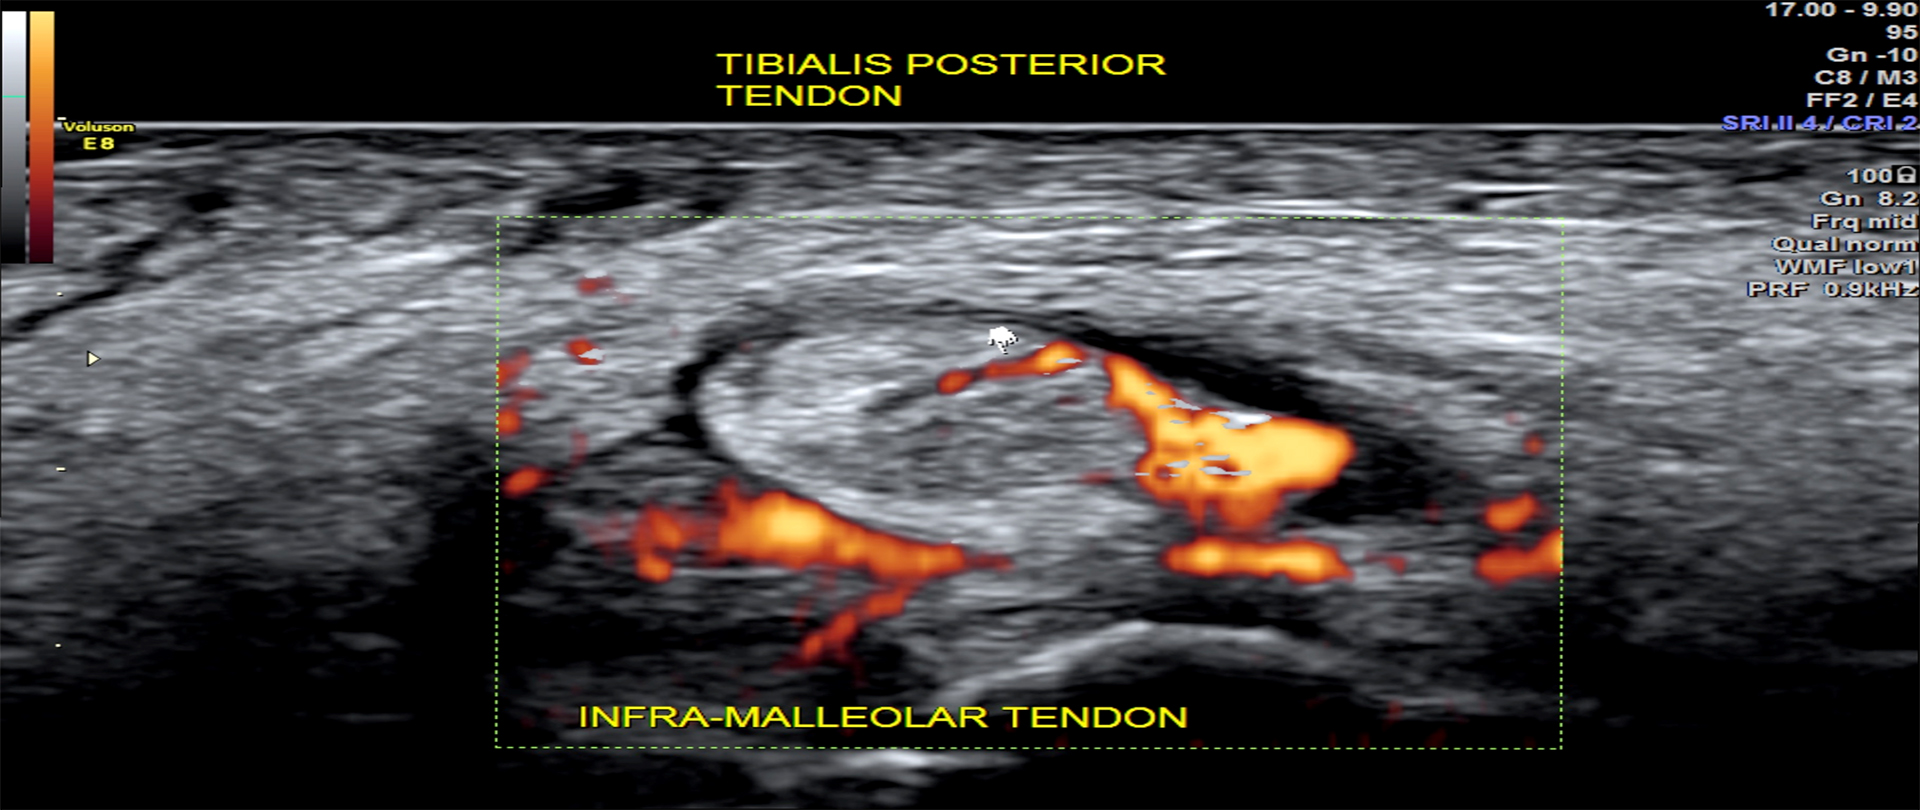

info.secretarymus@gmail.comThe recognition of MSK USG as a valuable clinical tool is neither automatic nor guaranteed. It is earned by maintaining quality control with positive results in clinical diagnosis, a goal that is obtainable only when high educational standards are met in the production of MSK sonographers and sonologists. The serious nature of MSK sonongraphy requires individuals who wish to become MSK sonographers to be exposed to both disciplines if they are to assume the responsibilities required of them in a quality MSK ultrasound setting.